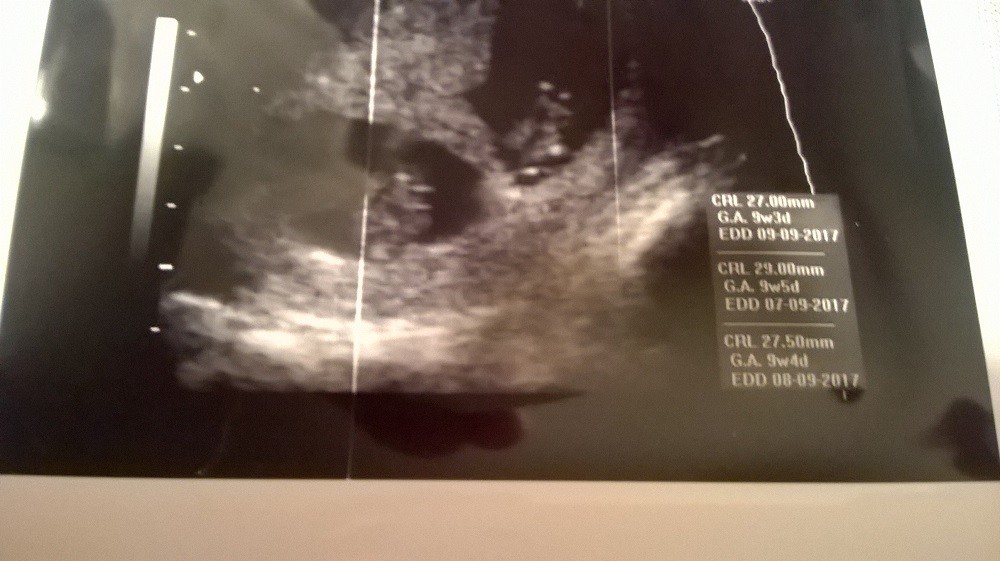

10 tc wedle OM

9 tc wedle usg

Zobacz załącznik 794679

Zobacz załącznik 794680